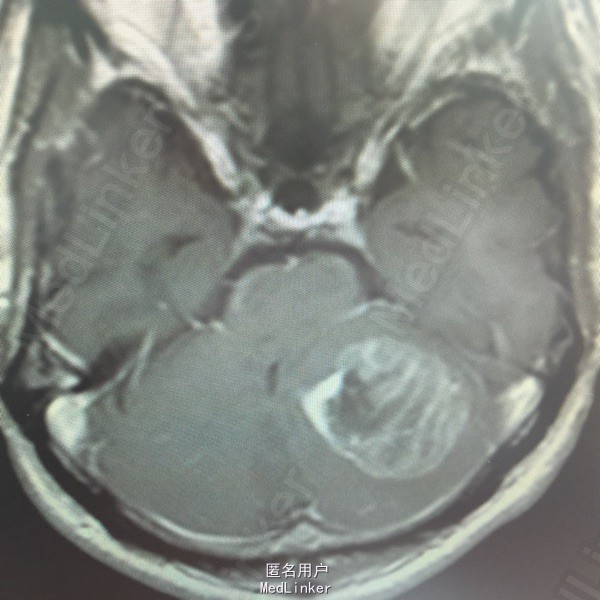

男,54岁,以头痛半个月入院。 现病史:半个月前无诱因头痛,呈胀痛,无呕吐,无意识障碍,病来咳嗽、咳痰,体重减轻约5斤,无发热。 既往史:无特殊。

查体:BP:150/100mmHg,神清语明,两瞳孔等大正圆,直径约3.0mm,光敏,四肢肌力5级,肌张力正常,腱反射艹,左侧共济运动阳性,病理征阳性,脑膜刺激征(-)。 辅查:见下:

肺癌脑转移。 影像解读(影像如何解读是临床工作中非常重要的一环)。 左侧额叶近皮质长Tl长T2信号,局部颅骨缺损,右侧枕叶不规则病灶,TlWl呈中心呈等信号,周围高信号,T2Wl呈高低混杂信号,伴大片水肿,相邻侧脑室后角、胼胝体受压。增强呈不规则环环强化。 已进行局部放疗治疗。